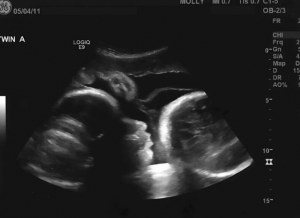

Kada je napokon odlučila da ode kod ginekologa, bila je sigurna da će uskoro roditi. Verovala je da je prošlo devet meseci, prema njenim proračunima. Međutim, kada je lekar video njen uzrast, bio je zabrinut, ali nije mogao ni da pretpostavi šta će otkriti. Uradio je nekoliko pregleda i, kada je pogledao slike na ekranu, njegovo lice postalo je bledo. Umesto bebe, ekran je prikazao nešto potpuno drugačije – nešto što nije imalo veze sa trudnoćom. Larisa nije mogla da veruje svojim očima. Testovi su pokazali pozitivnu trudnoću, ali zapravo je bilo reč o ozbiljnoj medicinskoj situaciji koja je uzrokovala rast njenog stomaka.

Larisa je bila u šoku. Sve što je verovala, sada se rušilo pred njenim očima. Na ekranu nije bilo ničega što bi ličilo na trudnoću. Lekar je odmah pozvao dodatne stručnjake, jer je stanje bilo ozbiljno. Uverio je Larisinu da je njen stomak rastao zbog medicinskog problema, a ne zbog trudnoće. Ovaj trenutak suočavanja sa stvarnošću bio je bolan za Larisinu, jer je toliko verovala u čudo da je zanemarivala stvarne simptome.